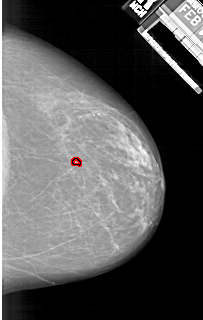

A_1925_1.LEFT_CC

LEFT_CC LINES 6061 PIXELS_PER_LINE 3616 BITS_PER_PIXEL 12 RESOLUTION 43.5 NON_OVERLAY

FILE: A_1925_1.RIGHT_MLO.OVERLAY

TOTAL_ABNORMALITIES 1

ABNORMALITY 1

LESION_TYPE CALCIFICATION TYPE PLEOMORPHIC DISTRIBUTION CLUSTERED

ASSESSMENT 4

SUBTLETY 3

PATHOLOGY BENIGN

TOTAL_OUTLINES 1

BOUNDARY